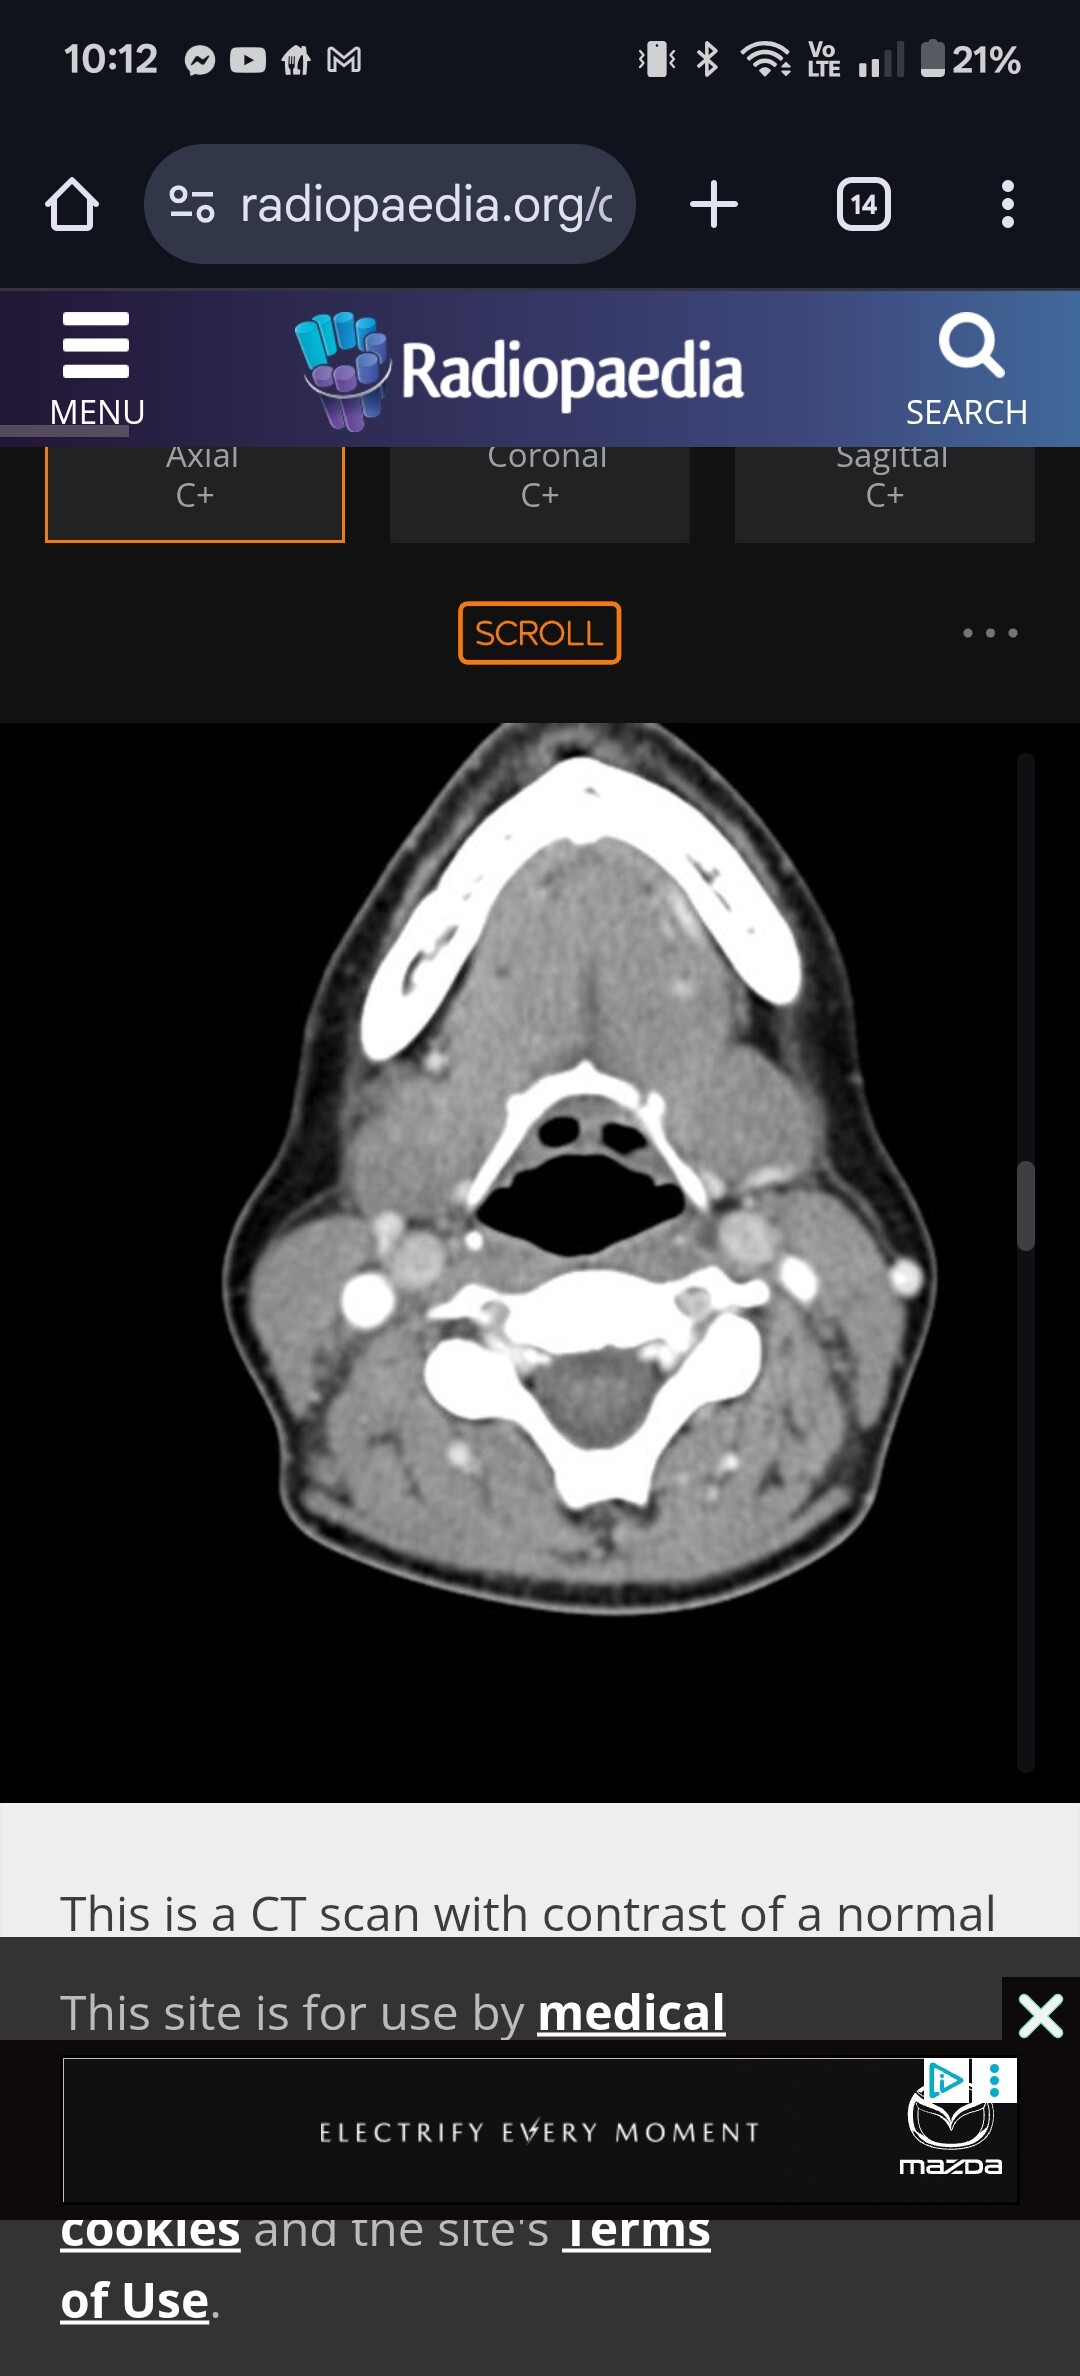

@BraveKat do you happen to have your CT imaging on hand? If you go to the axial view and go down to your hyoid bone I can see if your hyoid is digging into anything important! The axial view of the hyoid looks like this:

Hi, sorry for the delay in replying. Thank you for your message and for taking the time to look it over. My images aren’t as clear as yours unfortunately. I’m at the ER now as not feeling well at all today. Hope I can get some of this sorted. Fingers crossed!